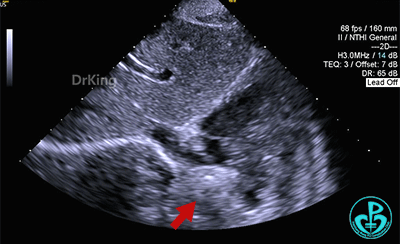

多切面观察封堵器位置形态,封堵器骑跨于缺损左右两侧。

准备锁定

锁定前,四腔心切面显示封堵器形态良好,牵拉试验,封堵器骑跨于缺损两侧,封堵器整体稳定,仅右盘随钢缆牵拉移动。